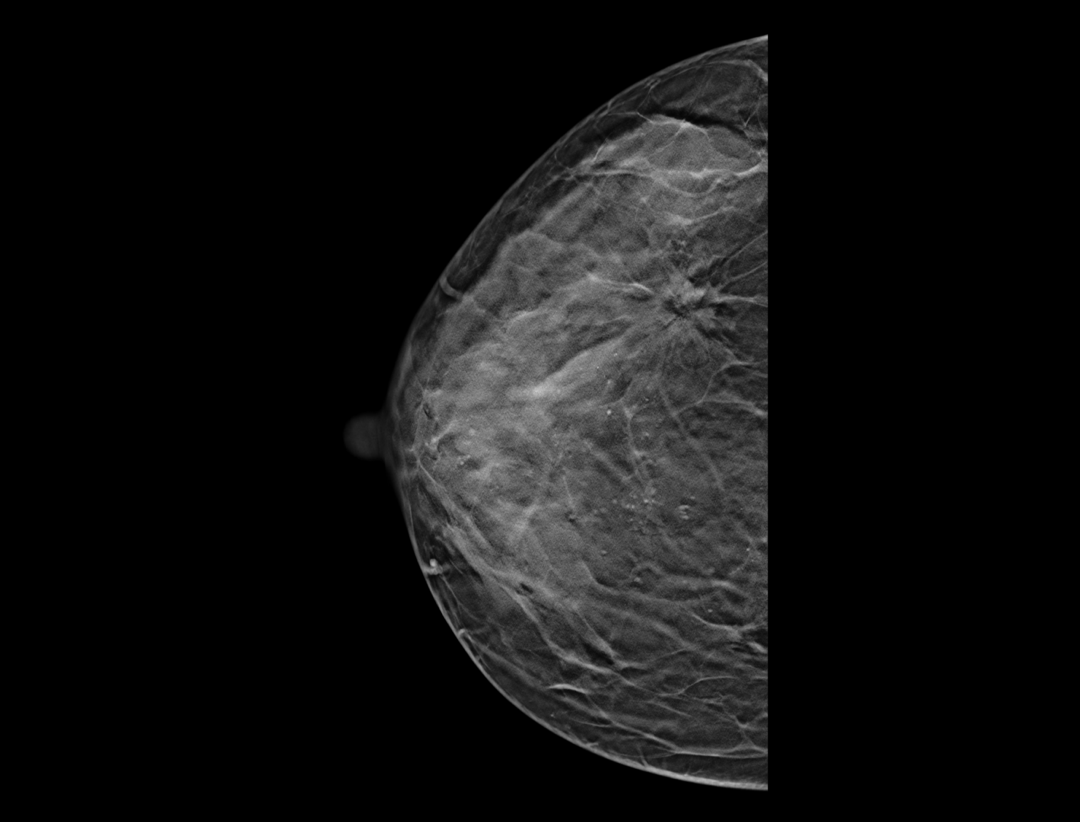

Adaptacyjne dostosowanie grubości warstwy tomosyntezy zapewnia szczegółowe obrazowanie przestrzenne zmian chorobowych i skupisk mikrozwapnień.

Wiele konfiguracji protokołów wyświetlania i wszechstronne narzędzia sprawiają, że przeglądanie mammografii cyfrowej jest bardziej elastyczne i uproszczone. Narzędzie lokalizatora pomaga użytkownikowi wskazać pozycje warstw tomosyntezy wewnątrz obrazu 3D.

Hybrydowe protokoły wyświetlania pozwalają na synchroniczne wyświetlanie obrazów 2D i warstw tomosyntezy w celu łatwego porównania. Dostępne są zarówno pogrubione warstwy (slabs), jak i widok płaszczyzny.